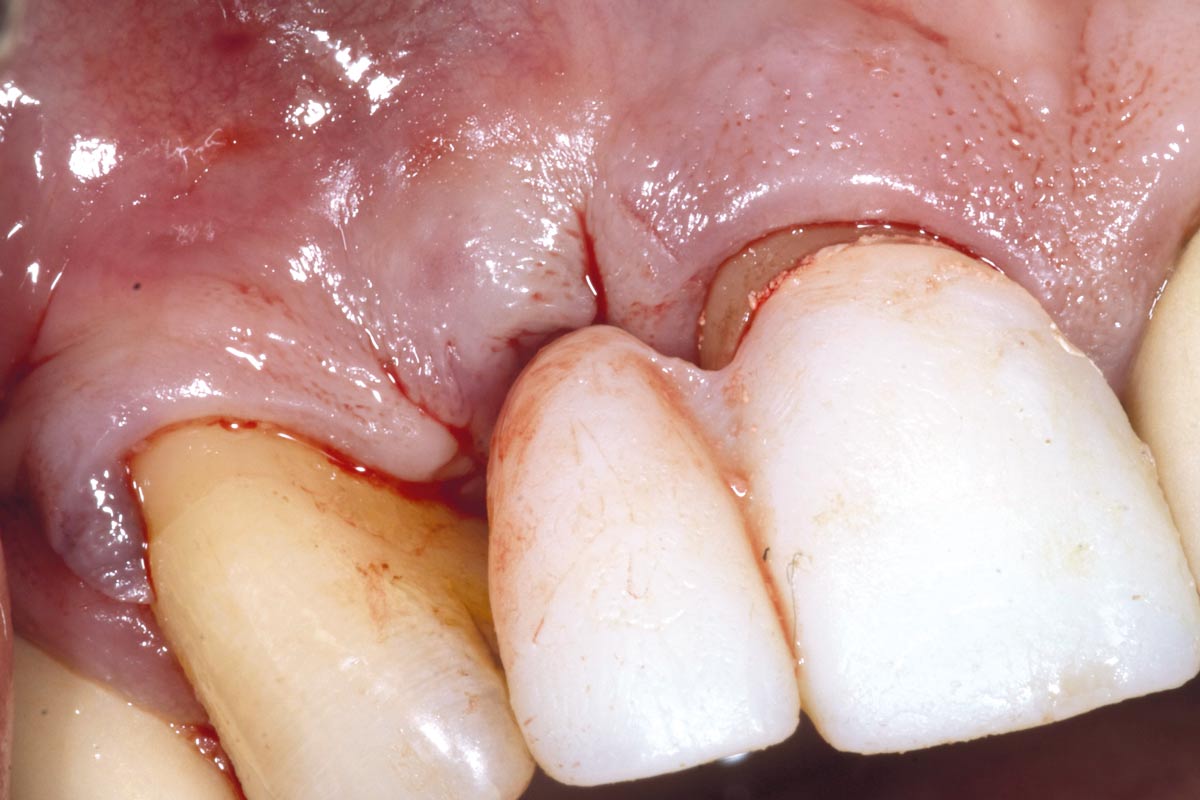

3/19 - Fracture of tooth while extractionBone augementation with maxresorb® - Dr. R. Cutts